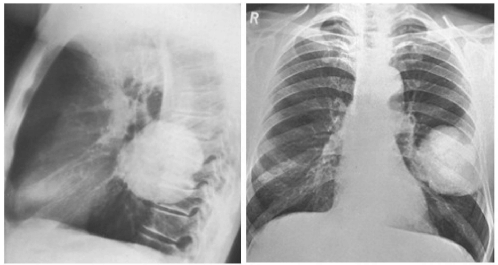

Paciente de sexo masculino, 50 anos, fumante, realizou radiografia de tórax frente e perfil abaixo. A partir das imagens assinale a alternativa correta quanto ao padrão, localização e provável natureza da lesão.